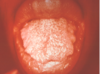

What is this clinical presentation?

Geographic tongue/

areata migrans